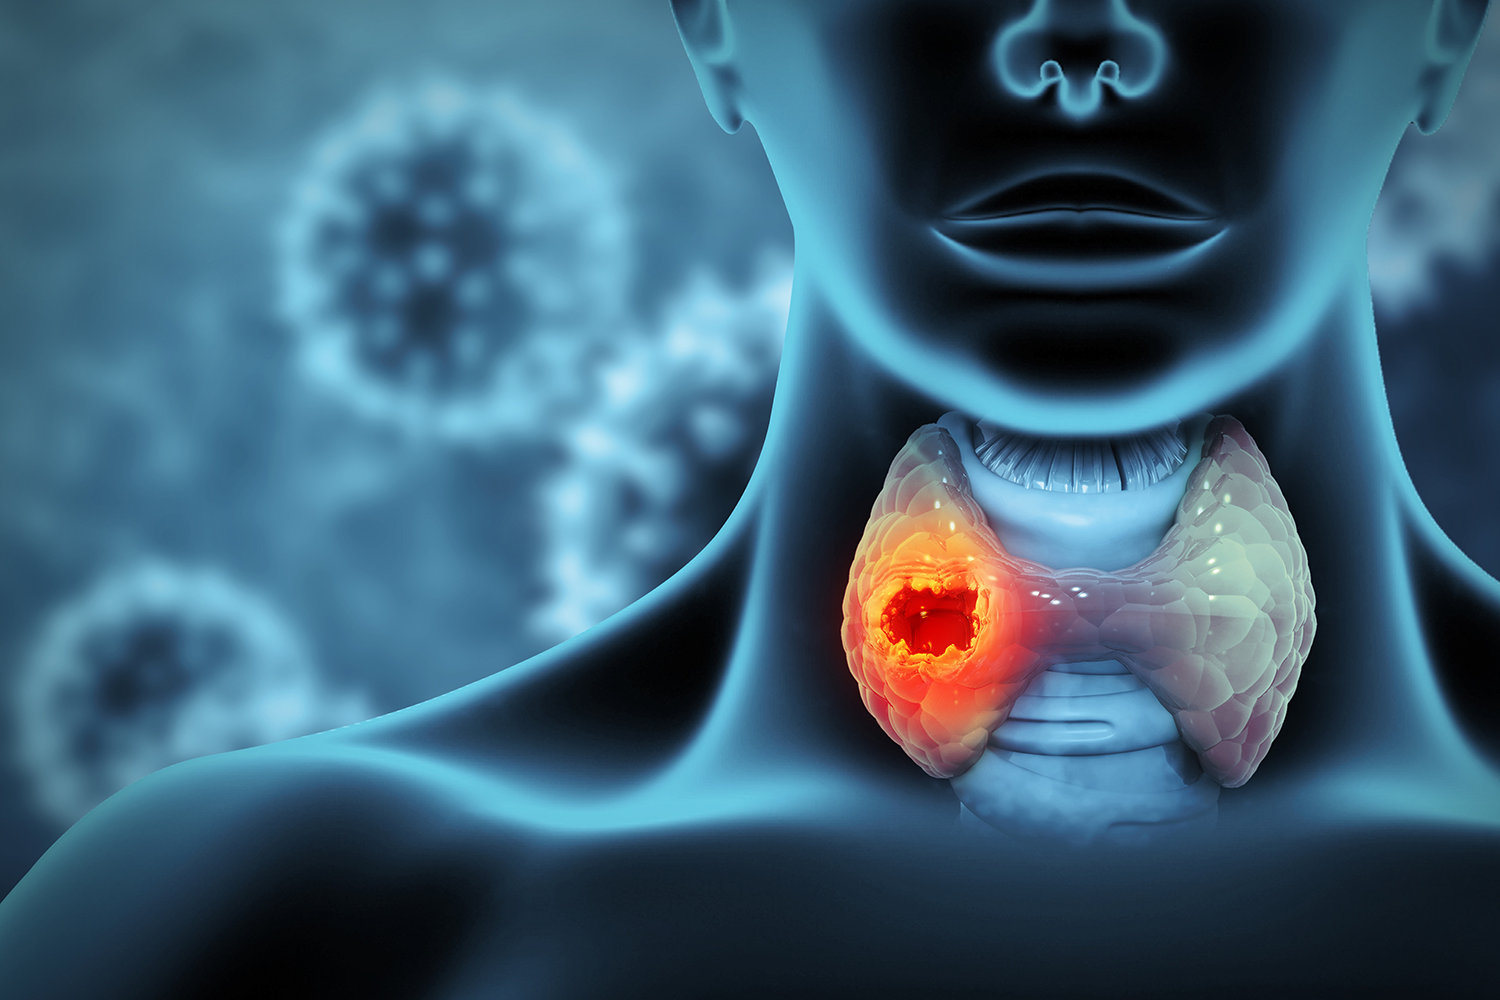

Pajzsmirigy szűrővizsgálatok Sopronban

Pajzsmirigy szűrővizsgálatok

Szinte nincs olyan szerv, amely funkcióját ne befolyásolná a pajzsmirigy hormon.

A pajzsmirigy élettani feladata a pajzsmirigy hormon termelése. A pajzsmirigy hormon szerepet játszik a szervezet anyagcseréjének szabályozásában, a növekedésben, a szexuális működésben, az agyi működésben. A pajzsmirigy hormon termelődése szükséges az élethez. Ugyanakkor túltermelődése életveszély állapotot, sőt halált is eredményezhet.

A Pannonia Medicalban mind laborvizsgálatok, mind ultrahang diagnosztika rendelkezésre áll a pajzsmirigy vizsgálatához!

Pajzsmirigy vizsgálatokról bővebben

Pajzsmirigy aspirációs citológia

Pajzsmirigy aspirációs citológia

mintavétel

Pajzsmirigy mintavételre akkor van szükség, ha előzetes orvosi, labor és főként ultrahang vizsgálattal rosszindulatúságra gyanús göb van a pajzsmirigyben. Az ultrahang az elsőként választandó módszer a pajzsmirigy képalkotó vizsgálatára. Ennek során szigorú kritériumok alapján osztályozzuk a göböket (a legmagasabb specificitási és szenzitivitási mutató az EU-TIRADS rendszert jellemzi), a pontrendszerek ismerete segíthet a pajzsmirigygöbök elkülönítésében, a mintavétel szükségességét eldönti, ezáltal csökkentheti az aspirációs citológiák számát, meghatározható a követés gyakorisága, mindezekkel támogatva a klinikai döntéshozatalt.

Bővebben a mintavételről